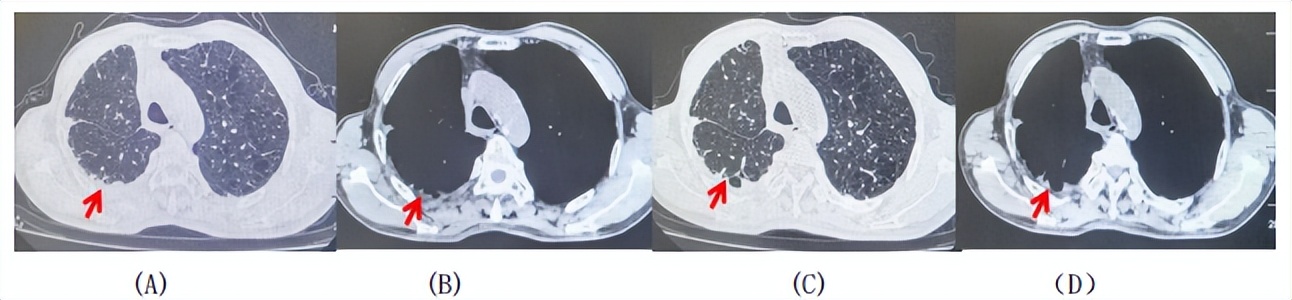

2024.11.19患者出现右侧胸痛,复查胸部CT检查示右侧胸膜肿物,大小约31mmX24mm,右侧4、5肋骨骨质破坏,考虑转移(如图2)。建议患者穿刺活检取病理明确诊断,患者拒绝,经MDT会诊后结合影像学表现及病史考虑为胸膜转移,肋骨转移,分期为rT0N0M1a IVA期,DFS仅仅17个月。2024.12.05起行信迪利单抗联合培美曲塞+卡铂方案治疗4周期,复查胸CT评效PR(如图3)。之后给予信迪利单抗+培美曲塞维持治疗6周期,期间复查CT评效PR(如图3)。目前信迪利单抗+培美曲塞维持治疗中,截止至目前PFS约为8个月,治疗期间未出现明显毒副反应。

图2:患者胸膜及肋骨转移(2024.11)胸部CT肺窗、纵隔窗及骨窗

图3:患者免疫联合化疗治疗后胸部CT,(A、B)图展示信迪利单抗联合培美曲塞+卡铂治疗

4周期(2025.02)疗效,(C、D)图展示信迪利单抗+培美曲塞维持治疗6周期(2025.07)疗效